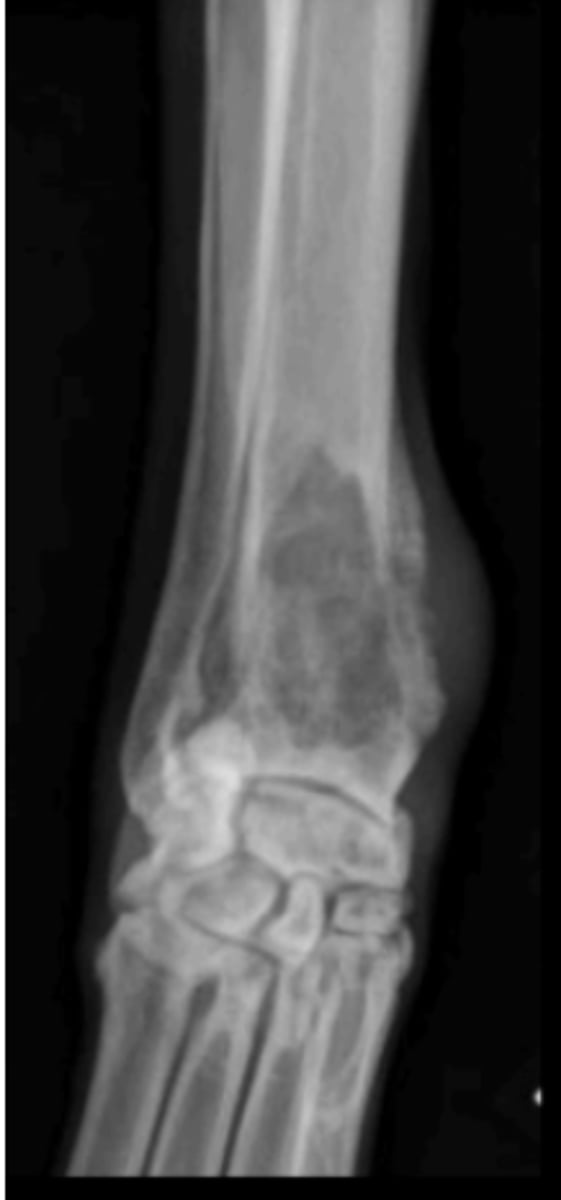

Type III

What fracture type is this?